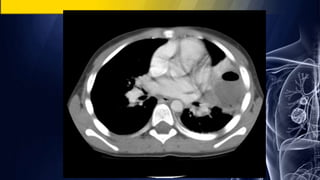

Asymptomatic 35-year-old man

• PA chest radiograph demonstrates a well-marginated polylobular mass in the

right lower lobe.

Coned-down contrast-enhanced chest CT (lung and mediastinal windows)

demonstrates a polylobular right lower lobe mass with well-defined borders and

intrinsic homogeneous fluid attenuation contents.

Pulmonary Cystic Hydatid Disease (Echinococcosis)

Asymptomatic 35-year-old man •PA chest radiograph demonstrates a well-marginated polylobular mass in the right lower lobe. Coned-down contrast-enhanced chest CT (lung and mediastinal windows) demonstrates a polylobular right lower lobe mass with well-defined borders and intrinsic homogeneous fluid attenuation contents. Pulmonary Cystic Hydatid Disease (Echinococcosis)